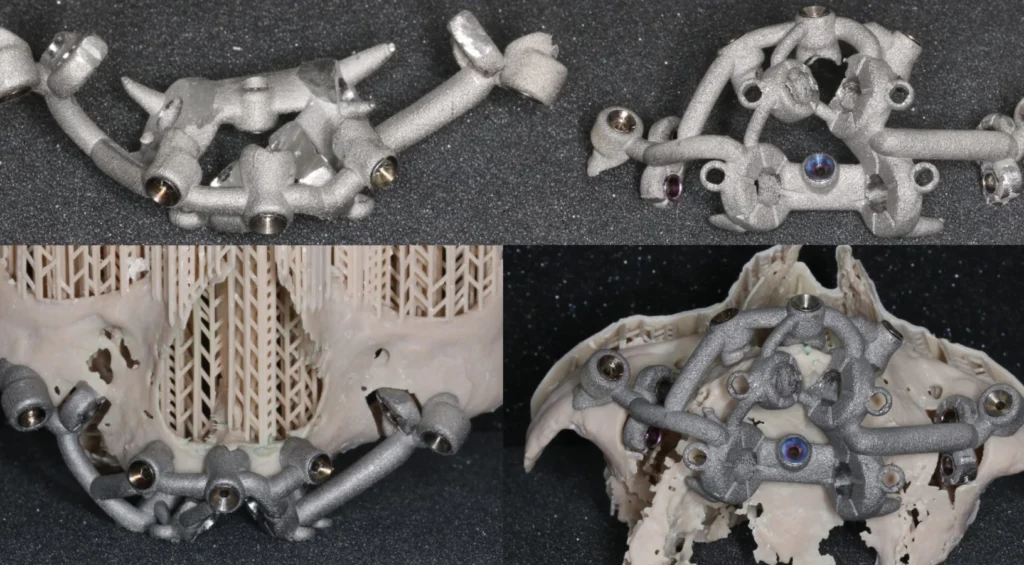

L’étude implantaire se fait à l’aide d’un logiciel de planification qui intègre le design de la future prothèse qui a été validé d’un point de vue esthétique et fonctionnel pour optimiser le placement des implants. Une fois validé un guide chirurgical en titane imprimé monobloc, est conçu pour reproduire lors de la chirurgie la position virtuelle des implants planifiés gage de plus de précision et de sécurité chirurgicale. C’est un guide à double douille qui stabilise le foret lors du passage dans le maxillaire puis dans le zygoma. L’extension zygomatique du guide est retirée après le forage pour laisser passer l’implant zygomatique guidé.